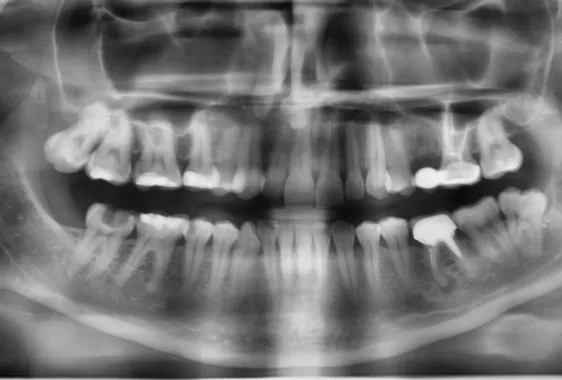

- Панорамный снимок (ортопантомограмма, ОПТГ). Охватывает верхнюю и нижнюю челюсти, включая зубы мудрости.

Ортопантомограмма необходима в следующих случаях:

- оценка строения и расположения зубных единиц в ряду;

- поиск кист, воспалений у корней;

- обследование суставов;

- лечение кариеса, пульпита;

- подготовка к коррекции прикуса, протезированию, хирургическим вмешательствам.

Если подытожить, панорамный снимок показывает общую картину, прицельный снимок – локальную. Выбор метода исследования зависит от запланированной процедуры.